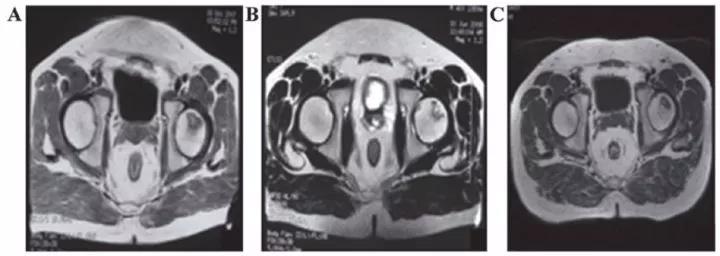

吉林省組織工程重點實驗室劉穎教授 、首都醫(yī)科大學(xué)宣武醫(yī)院谷涌泉主任等,對9位骨循環(huán)協(xié)會評級為II-IIIa級的股骨頭壞死患者經(jīng)大腿動脈輸注臍帶間充質(zhì)干細(xì)胞后,患者的紅細(xì)胞、血小板、血氧轉(zhuǎn)運(yùn)指數(shù)明顯改善。MRI檢測顯示24個月后股骨頭壞死區(qū)域體積顯著減少。